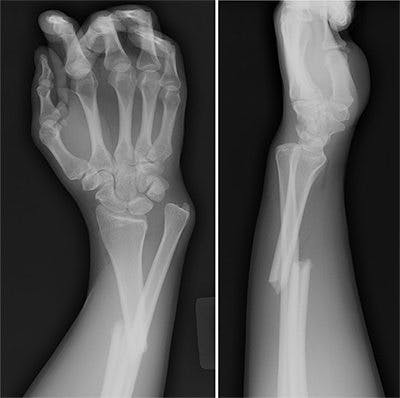

Även om hon nu har en opublicerad interventionsstudie som inte visat effekt är det ändå ett tveksamt uttalande. Ett dussintal studier av högsta klass (dubbelblinda RCT) på sammanlagt över 40,000 personer visar redan tydligt att tillskott av D-vitamin skyddar mot benbrott. Oavsett vad Snellmans eventuella nya undersökning visat så lär den knappast vända upp och ner på all tidigare forskning.